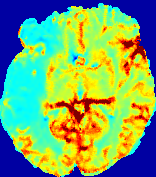

LesionRefer to captionRefer to captionRefer to captionRefer to captionRefer to captionRefer to caption𝐕rgbsubscript𝐕𝑟𝑔𝑏{\bf{V}}_{rgb}Refer to captionRefer to captionRefer to captionRefer to captionRefer to captionRefer to caption𝐕2subscriptnorm𝐕2{\|\bf{V}}\|_{2}Refer to captionRefer to captionRefer to captionRefer to captionRefer to captionRefer to captionRefer to caption3.53.53.52.82.82.82.12.12.11.41.41.40.70.70.70.00.00.0(mm/s)𝑚𝑚𝑠(mm/s)D𝐷DRefer to captionRefer to captionRefer to captionRefer to captionRefer to captionRefer to captionRefer to caption0.0200.0200.0200.0160.0160.0160.0120.0120.0120.0080.0080.0080.0040.0040.0040.0000.0000.000(mm2/s)𝑚superscript𝑚2𝑠(mm^{2}/s)Slice #1Slice #2Slice #3Slice #4Slice #5Slice #6

Figure 3: PIANO feature maps for one stroke patient, where the lesion is located in the left hemisphere. Top row: segmented stroke lesion region (white) on different slices, obtained from ISLES 2017. The corresponding slices for the PIANO feature maps are shown in the following rows.

For a better insight into an estimated velocity field 𝐕𝐕{\bf{V}} and diffusion field 𝐃𝐃{\bf{D}}, we compute the following maps: (1) 𝐕rgbsubscript𝐕𝑟𝑔𝑏{\bf{V}}_{rgb}: Color-coded orientation map of 𝐕=(Vx,Vy,Vz)T𝐕superscriptsuperscript𝑉𝑥superscript𝑉𝑦superscript𝑉𝑧𝑇{\bf{V}}=(V^{x},V^{y},V^{z})^{T}, obtained by normalizing 𝐕𝐕{\bf{V}} to unit length and mapping its 3 components to red, green, blue respectively; (2) 𝐕2subscriptnorm𝐕2\|{\bf{V}}\|_{2}: 222 norm of 𝐕𝐕{\bf{V}}; (3) D𝐷D: scalar field in Eq. 5.

Fig. 3 and Fig. 4 show the PIANO feature maps estimated from two ISLES 2017 patients: all are highly consistent with the lesion in both cases. Details of the blood flow trajectories are revealed in 𝐕rgbsubscript𝐕𝑟𝑔𝑏{\bf{V}}_{rgb} by the ridged patterns and the sharp changes of colors in the unaffected (right) hemisphere, while the flat patterns appearing within the lesion provide little directional information about the velocity and indicate low velocity magnitudes. Velocity magnitudes are more directly visualized via 𝐕2subscriptnorm𝐕2\|{\bf{V}}\|_{2}, from which one can easily locate the lesion where 𝐕2subscriptnorm𝐕2\|{\bf{V}}\|_{2} is low. D𝐷D also indicates lower diffusion values in the lesion, though with less contrast potentially due to the fact that it captures the accumulated effect of CA diffusion at the voxel-level.